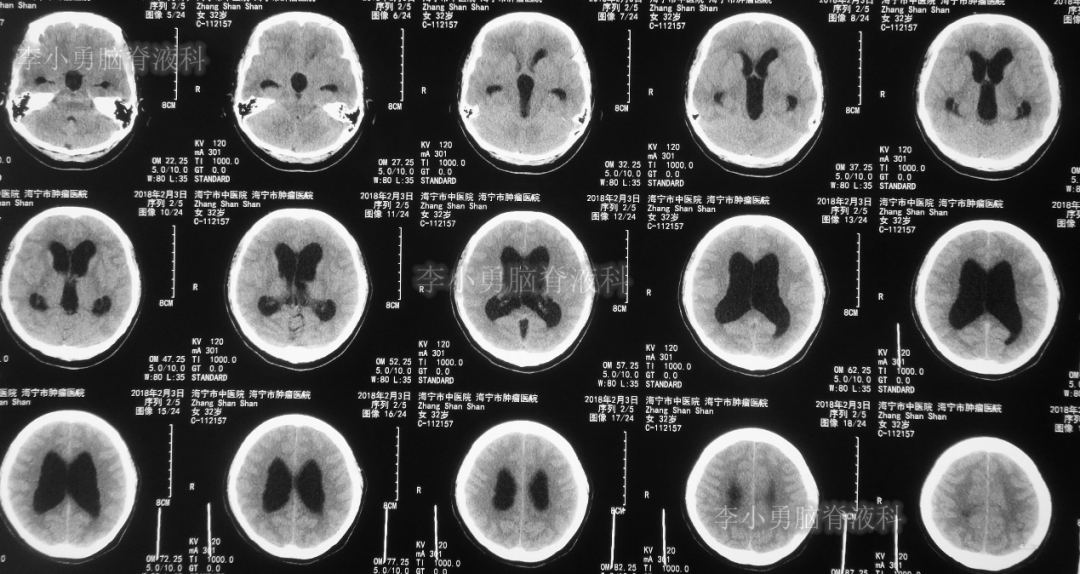

又2天后,即2018年2月5日,为求更好的治疗,患者转到第2家医院:浙江省杭州市的某三甲医院就诊,行头颅增强核磁共振检查(图-2)提示双侧脑室及第三脑室扩张,中脑导水管形态消失,第四脑室无扩张,未见颅内占位病变。

图-2:2018年2月5日头颅核磁